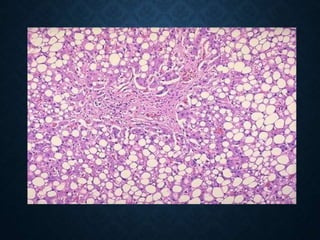

FAT CHANGE

fat metamorphosis or fat

transformation or steatosis

• Abnormal accumulation of neutral fats,

most often triglycerides, in the cytoplasm of

parenchymal cells that microscopically do

not contain fats (liver, heart muscle,

kidneys, skeletal muscles).

• Most often a reversible change

Steatosis hepatis

HISTOLOGICALLY

• macrovesicular-macrovesicular fatty change

• small droplet-microvesicular

• diffuse

• zonal